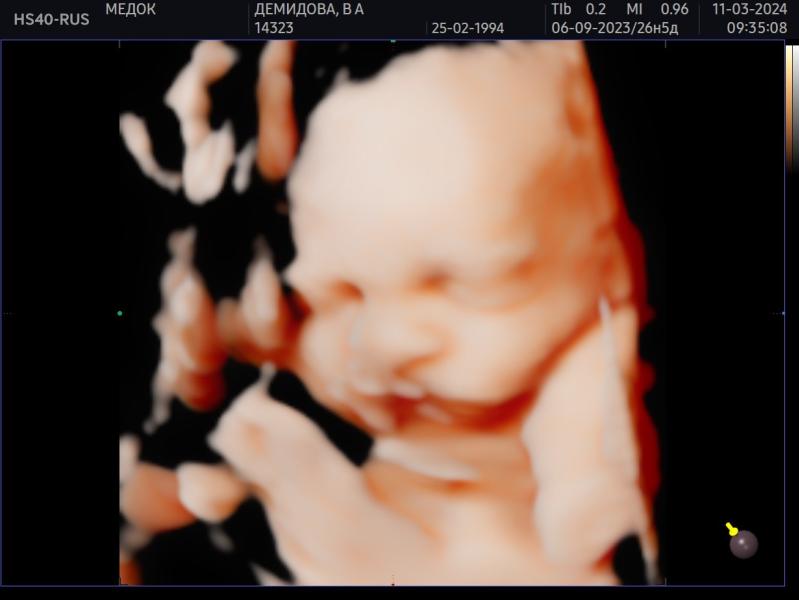

Была сегодня на 3д/4д узи в своей клинике, где веду беременность - Медок Марфино. Узист Лункина ЕГ (вдруг кто тоже туда планирует идти).

Проходила у нее два скрининга, будет у нее же третий, и вот сегодня промежуточное узи.

Срок 27.5 по 1 скринингу, так и опережаем месячные на неделю.

Сын весит около 1163 г. Ваши детки сколько весили на таком сроке?

Врач говорит что хороший вес для этого срока.

В целом все в порядке, лоханки так и остались слегка расширены, но врач сказала это не страшно. ...